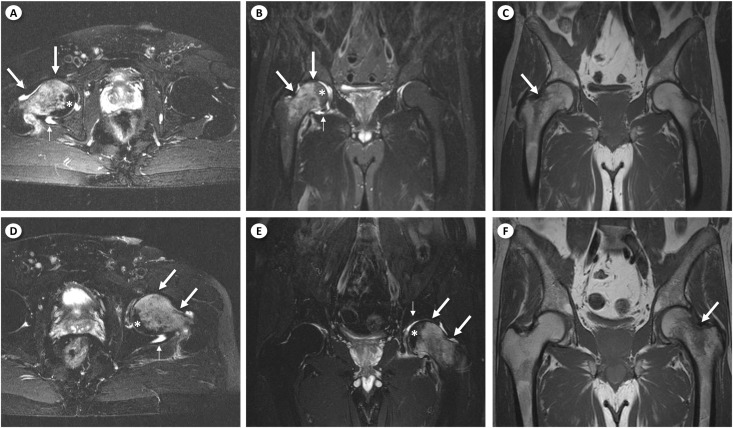

Regional Migratory Osteoporosis.